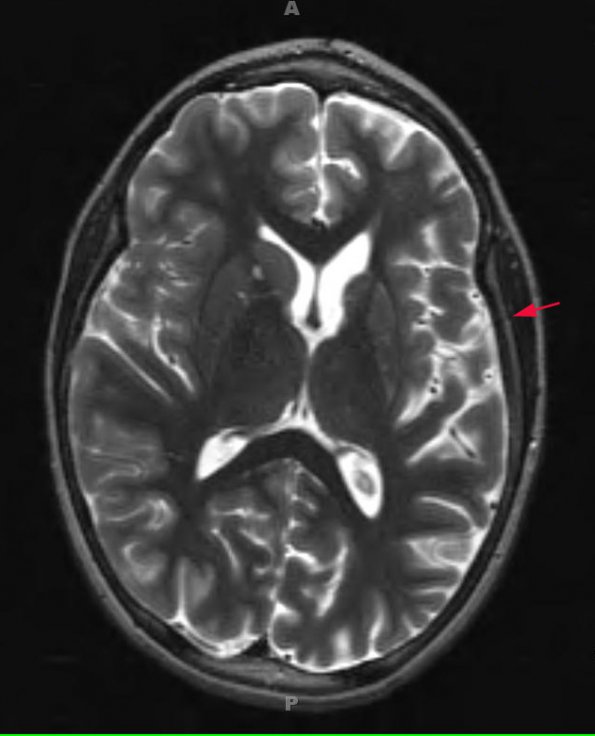

MRIs show atrophy and hydrocephalus ex vacuo (arrow marks involved side)